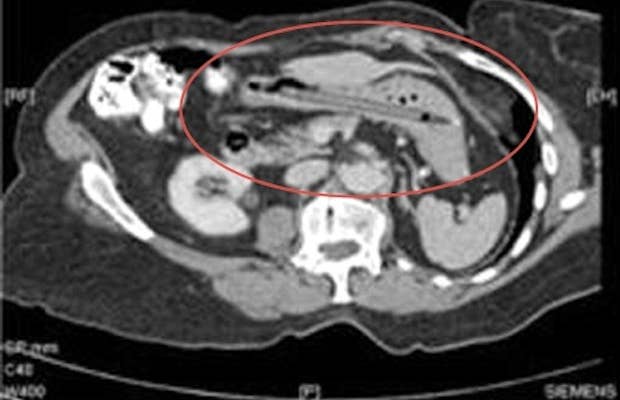

The pen was discovered in her stomach by CT scan after she went to the doctor's complaining of diarrhea. She recalled "unintentionally" swallowing a pen 25 years ago while she was trying to prod at a spot on one of her tonsils with it. From the British Medical Journal, "Her husband and general practitioner dismissed her story and plain abdominal films done at the time were reported as normal."